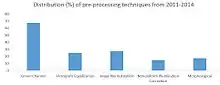

Because fundoscopic images are the main sources for diagnosis of diabetic retinopathy, manually analyzing those images can be time-consuming and unreliable, as the ability of detecting abnormalities varies by years of experience.[67] Therefore, scientists have explored developing computer-aided diagnosis approaches to automate the process, which involves extracting information about the blood vessels and any abnormal patterns from the rest of the fundoscopic image and analyzing them.[65]